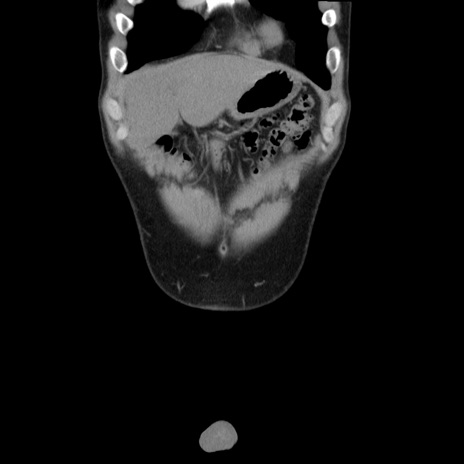

症例36(冠状断像)

【症例】20歳代 男性

【主訴】心窩部痛

【現病歴】今朝より上腹部痛あり。一旦軽快していたが再度出現したため救急要請。昨日夕に白身の魚を含む刺身を食べた。

【身体所見】BP 136/89mmHg、HR 74/min、BT 37.0℃、腹部:膨満、軟、心窩部に圧痛あり。反跳痛なし、筋性防御なし、腸雑音やや亢進あり。

【データ】WBC 17700、CRP 0.48